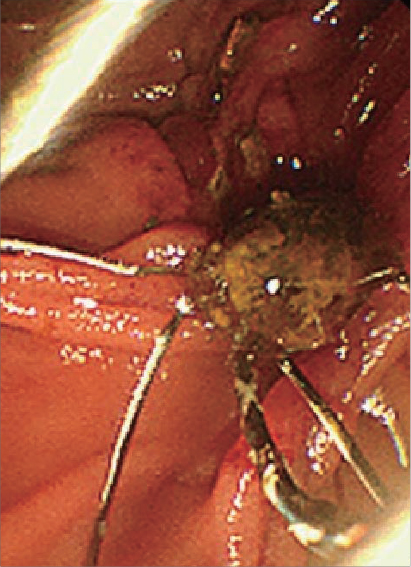

Image of a Stone Being Grasped

Begin retrieval from the stone at the bottom. Slowly open the basket so as not to push the stone at the top into a deeper area. The key is to withdraw the sheath toward the proximal end at the same time as opening the basket.

Endoscopic image courtesy of Dr. Ichiro Yasuda, MD

Endoscopic image

Making Use of Basket's Expansive Force by Scraping off Stones